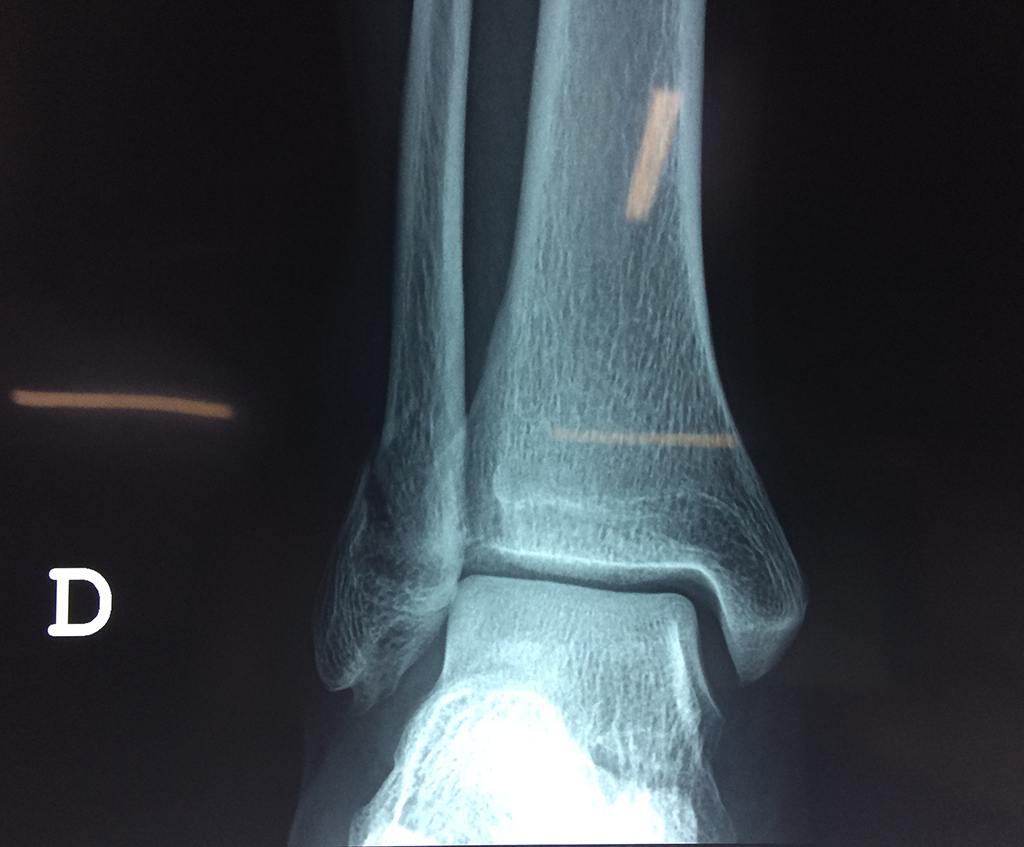

Una fractura de tobillo es la rotura de uno o más de los huesos del tobillo. Estas fracturas pueden ser:

- Parciales (el hueso está sólo parcialmente fisurado, no del todo).

- Completas (el hueso está perforado y está en 2 partes).

- Producirse en uno o ambos lados del tobillo.

Algunas fracturas de tobillo pueden requerir cirugía si:

- Los extremos de los huesos están desalineados entre sí (desplazados).

- La fractura se extiende hasta la articulación del tobillo (fractura intra-articular).

Cuando se necesita cirugía, es probable que esta implique el uso de clavijas de metal, tornillos o placas para sostener los huesos en su lugar mientras la fractura se consolida. Los elementos de soporte pueden ser temporales o permanentes.